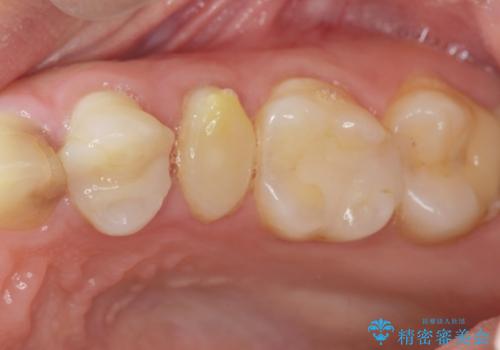

挺出小矯正を行った縁下カリエス治療

- 治療途中で虫歯治療を放置し、違和感が強くなってきたためしっかりとした虫歯治療を行いたいと希望され来院されました。

X線撮影を行い、隣接面に多発した虫歯と歯ぐきよりも深くなってしまった虫歯を小矯正をおこなったのちのセラミック治療で問題を解決します。